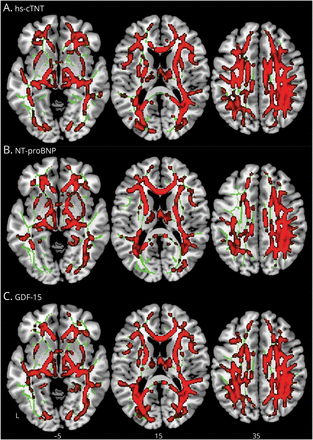

WM FW voxel-wise分析指标表明,更大的心血管生物标志物水平(中位数水平以上病人、hs-cTnT GDF-15)与更高的弗兰克-威廉姆斯在多个WM区域(包括投影、协会、连合、边缘和脑干纤维)在所有CIND和痴呆患者在基线(图2,eTable 5,links.lww.com/WNL/C813)。没有交互效应的认知阶段或CeVD状态等。没有区域显示协会血液生物标志物的WM FW NCI不管CeVD地位。

的整个大脑voxel-wise线性回归表明,更高的弗兰克-威廉姆斯在广泛的脑白质区域值与水平的提高(一)hs-cTNT NTpro-BNP (B)和(C) GDF-15。结果TFCE增强,在报道p< 0.01,FWE纠正。弗兰克-威廉姆斯=自由水;FWE = family-wise错误;GDF-15 15 =增长/分化因素;hs-cTnT =高灵敏度心脏临床;中位数水平以上病人= n端pro激素b型利钠肽;TFCE = threshold-free集群增强。

结果仍然当(1)控制区域WM卷(eFigure 4,links.lww.com/WNL/C813协变量),(2)控制vascular-related (eFigure 4 b),和(3)在正常使用弗兰克-威廉姆斯WM排除地区负责人(eResults)。此外,没有血液协会心血管生物标记和WM组织间脂肪水平。GDF-15,但不是中位数水平以上病人和hs-cTNT相关负责人总额(r= 0.19,95%置信区间0.07 - -0.31,p< 0.05)。